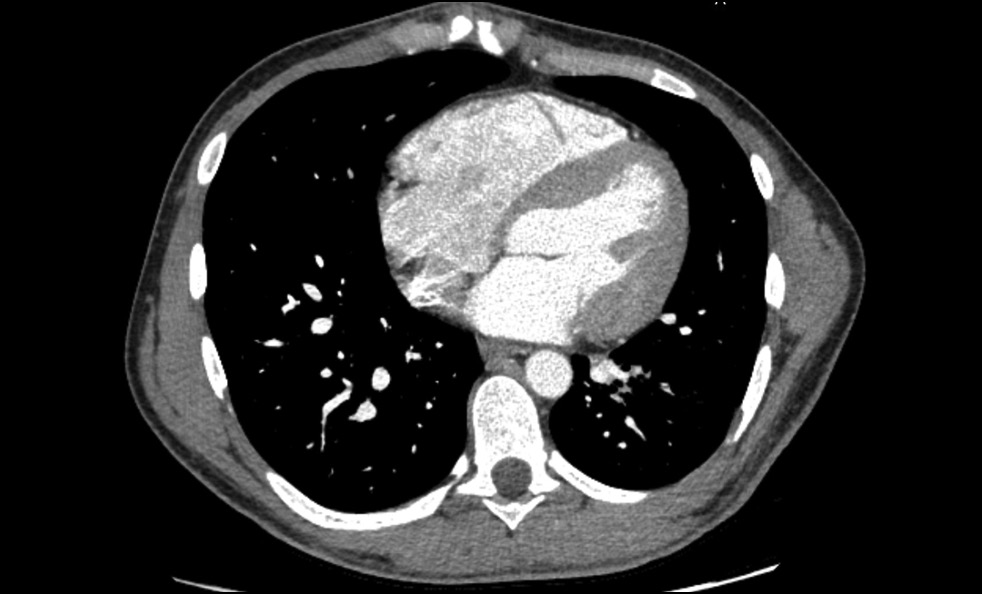

CT pulmonary angiogram showed no abnormal vascular shunts, but confirmed pulmonary trunk dilatation (diameter, 40 mm) (Figure 5), heart chamber dilatation, and myocardial hypertrophy (Figure 6).

Fig. 5. CT pulmonary angiography, axial view. Pulmonary trunk dilatation.

Fig. 6. CT pulmonary angiography, axial view. Myocardial hypertrophy.